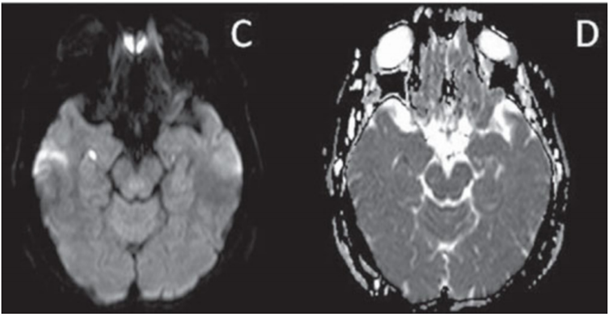

Paciente de 60 anos, sexo masculino, hipertenso, apresentou quadro de desorientação temporal e espacial de início súbito, acompanhado de cefaleia leve, sem perda de consciência, com duração de 12 horas. Foi submetido a exame de ressonância magnética do encéfalo dois dias após o início do quadro, estando disponíveis as seguintes imagens: A - T2; B - FLAIR; C - difusão; D - mapa de ADC.

Assinale a alternativa correta, que contém o diagnóstico para o quadro apresentado acima.